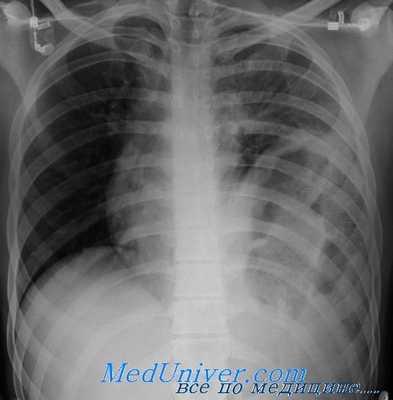

Рисунок 1. Анатомия диафрагмы и ее крупных отверстий Рисунок 2. А, Б. Грыжа левой половины диафрагмы после колотого ранения левой торакоабдоминальной области много лет назад: в левой части грудной клетки видны желудок и ободочная кишка Рисунок 3. А. Проникающее ранение левой половины диафрагмы (кружок). Рваная рана при проникающей травме довольно небольшая, обычно около 3—4 см в длину. Б. Разрыв левой половины диафрагмы в результате тупой травмы (стрелки). Разрыв при тупой травме крупный, обычно около 7—8 см в длину. Травмы, обусловленные замедлением, могут вызвать отрыв диафрагмы от мест ее прикрепления Рисунок 4. Все бессимптомные проникающие ранения левой торакоабдоминальной области между соском и нижним краем реберной дуги требуют проведения лапароскопии, чтобы исключить повреждение диафрагмы

• При отсутствии лечения повреждения диафрагмы могут привести к формированию диафрагмальной грыжи, которая манифестирует клиническими симптомами спустя долгое время после травмы (рис. 2, А, Б).

• Травматические диафрагмальные грыжи почти всегда возникают в левой половине диафрагмы, хотя в редких случаях они могут формироваться при больших разрывах правой половины диафрагмы вследствие тупой травмы или небольших колотых ран в ее передней части.